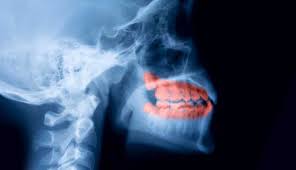

When the enamel—the hard protective shell of your teeth—breaks down due to plaque and bacteria, decay sets in.

Over time, this damage forms cavities that grow deeper, weaken the tooth from the inside out, and can eventually cause infections, severe pain, and tooth loss.

As decay reaches the inner layers of the tooth, bacteria can invade the pulp and nerves, causing swelling, abscesses, and even facial inflammation.